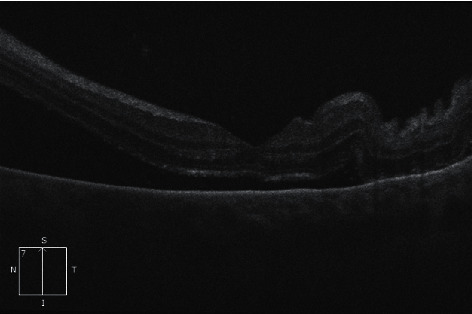

我们为大家介绍一例罕见病例:一名 39 岁女性在接受异体造血干细胞移植 2 个月后,左眼孤立性急性髓性白血病(AML)髓外复发。她最初出现无痛性左眼红斑、肿胀和视力障碍。眼科初步检查发现结膜化生、眼压升高和浆液性视网膜脱离。她最初因疑似眼眶蜂窝组织炎接受了静脉注射抗生素和抗真菌治疗,但临床症状有所进展,因此又接受了静脉注射皮质类固醇治疗。一周后,她的病情发展为闭角型青光眼,出现了眼睑下垂和结膜下肿块增大。她接受了紧急结膜下活检和视网膜下积液引流,结果证实急性髓外性白血病复发。值得注意的是,进一步检查没有发现骨髓或中枢神经系统复发的证据。她接受了局部放疗,结膜下肿块和浆液性视网膜脱离逐渐消退,并考虑接受供体淋巴细胞输注和阿扎胞苷治疗;不幸的是,她出现了呼吸道败血症,虽经全力抢救仍不幸去世。本病例是急性髓细胞性白血病孤立性眼部髓外复发的罕见病例,强调了临床高度怀疑该病时早期眼科介入和组织活检的重要性。

We present a rare case of a 39-year-old female with extramedullary relapse of acute myeloid leukaemia (AML) isolated to the left eye 2 months post allogeneic haematopoietic stem cell transplant. She initially presented with painless left eye erythema, swelling, and visual impairment. Initial ophthalmology review revealed conjunctival chemosis, raised intraocular pressure, and serous retinal detachments. She was initially treated for suspected orbital cellulitis with intravenous antibiotic and antifungal therapy but clinically progressed so was then treated with intravenous corticosteroids. One week later, she progressed to angle-closure glaucoma with development of a hypopyon and an enlarging subconjunctival mass. She proceeded to urgent subconjunctival biopsy and drainage of subretinal fluid which confirmed extramedullary relapse of AML. Notably, further investigation found no evidence of bone marrow or central nervous system relapse. She proceeded to localized radiotherapy with gradual resolution of the subconjunctival mass and serous retinal detachment and was for consideration of donor lymphocyte infusions and azacitidine therapy; unfortunately, she developed respiratory sepsis and passed away despite maximal efforts. This case represents a rare and unusual presentation of isolated ocular extramedullary relapse of AML and emphasises the importance of early ophthalmology involvement and tissue biopsy when there is high clinical suspicion of the disease.